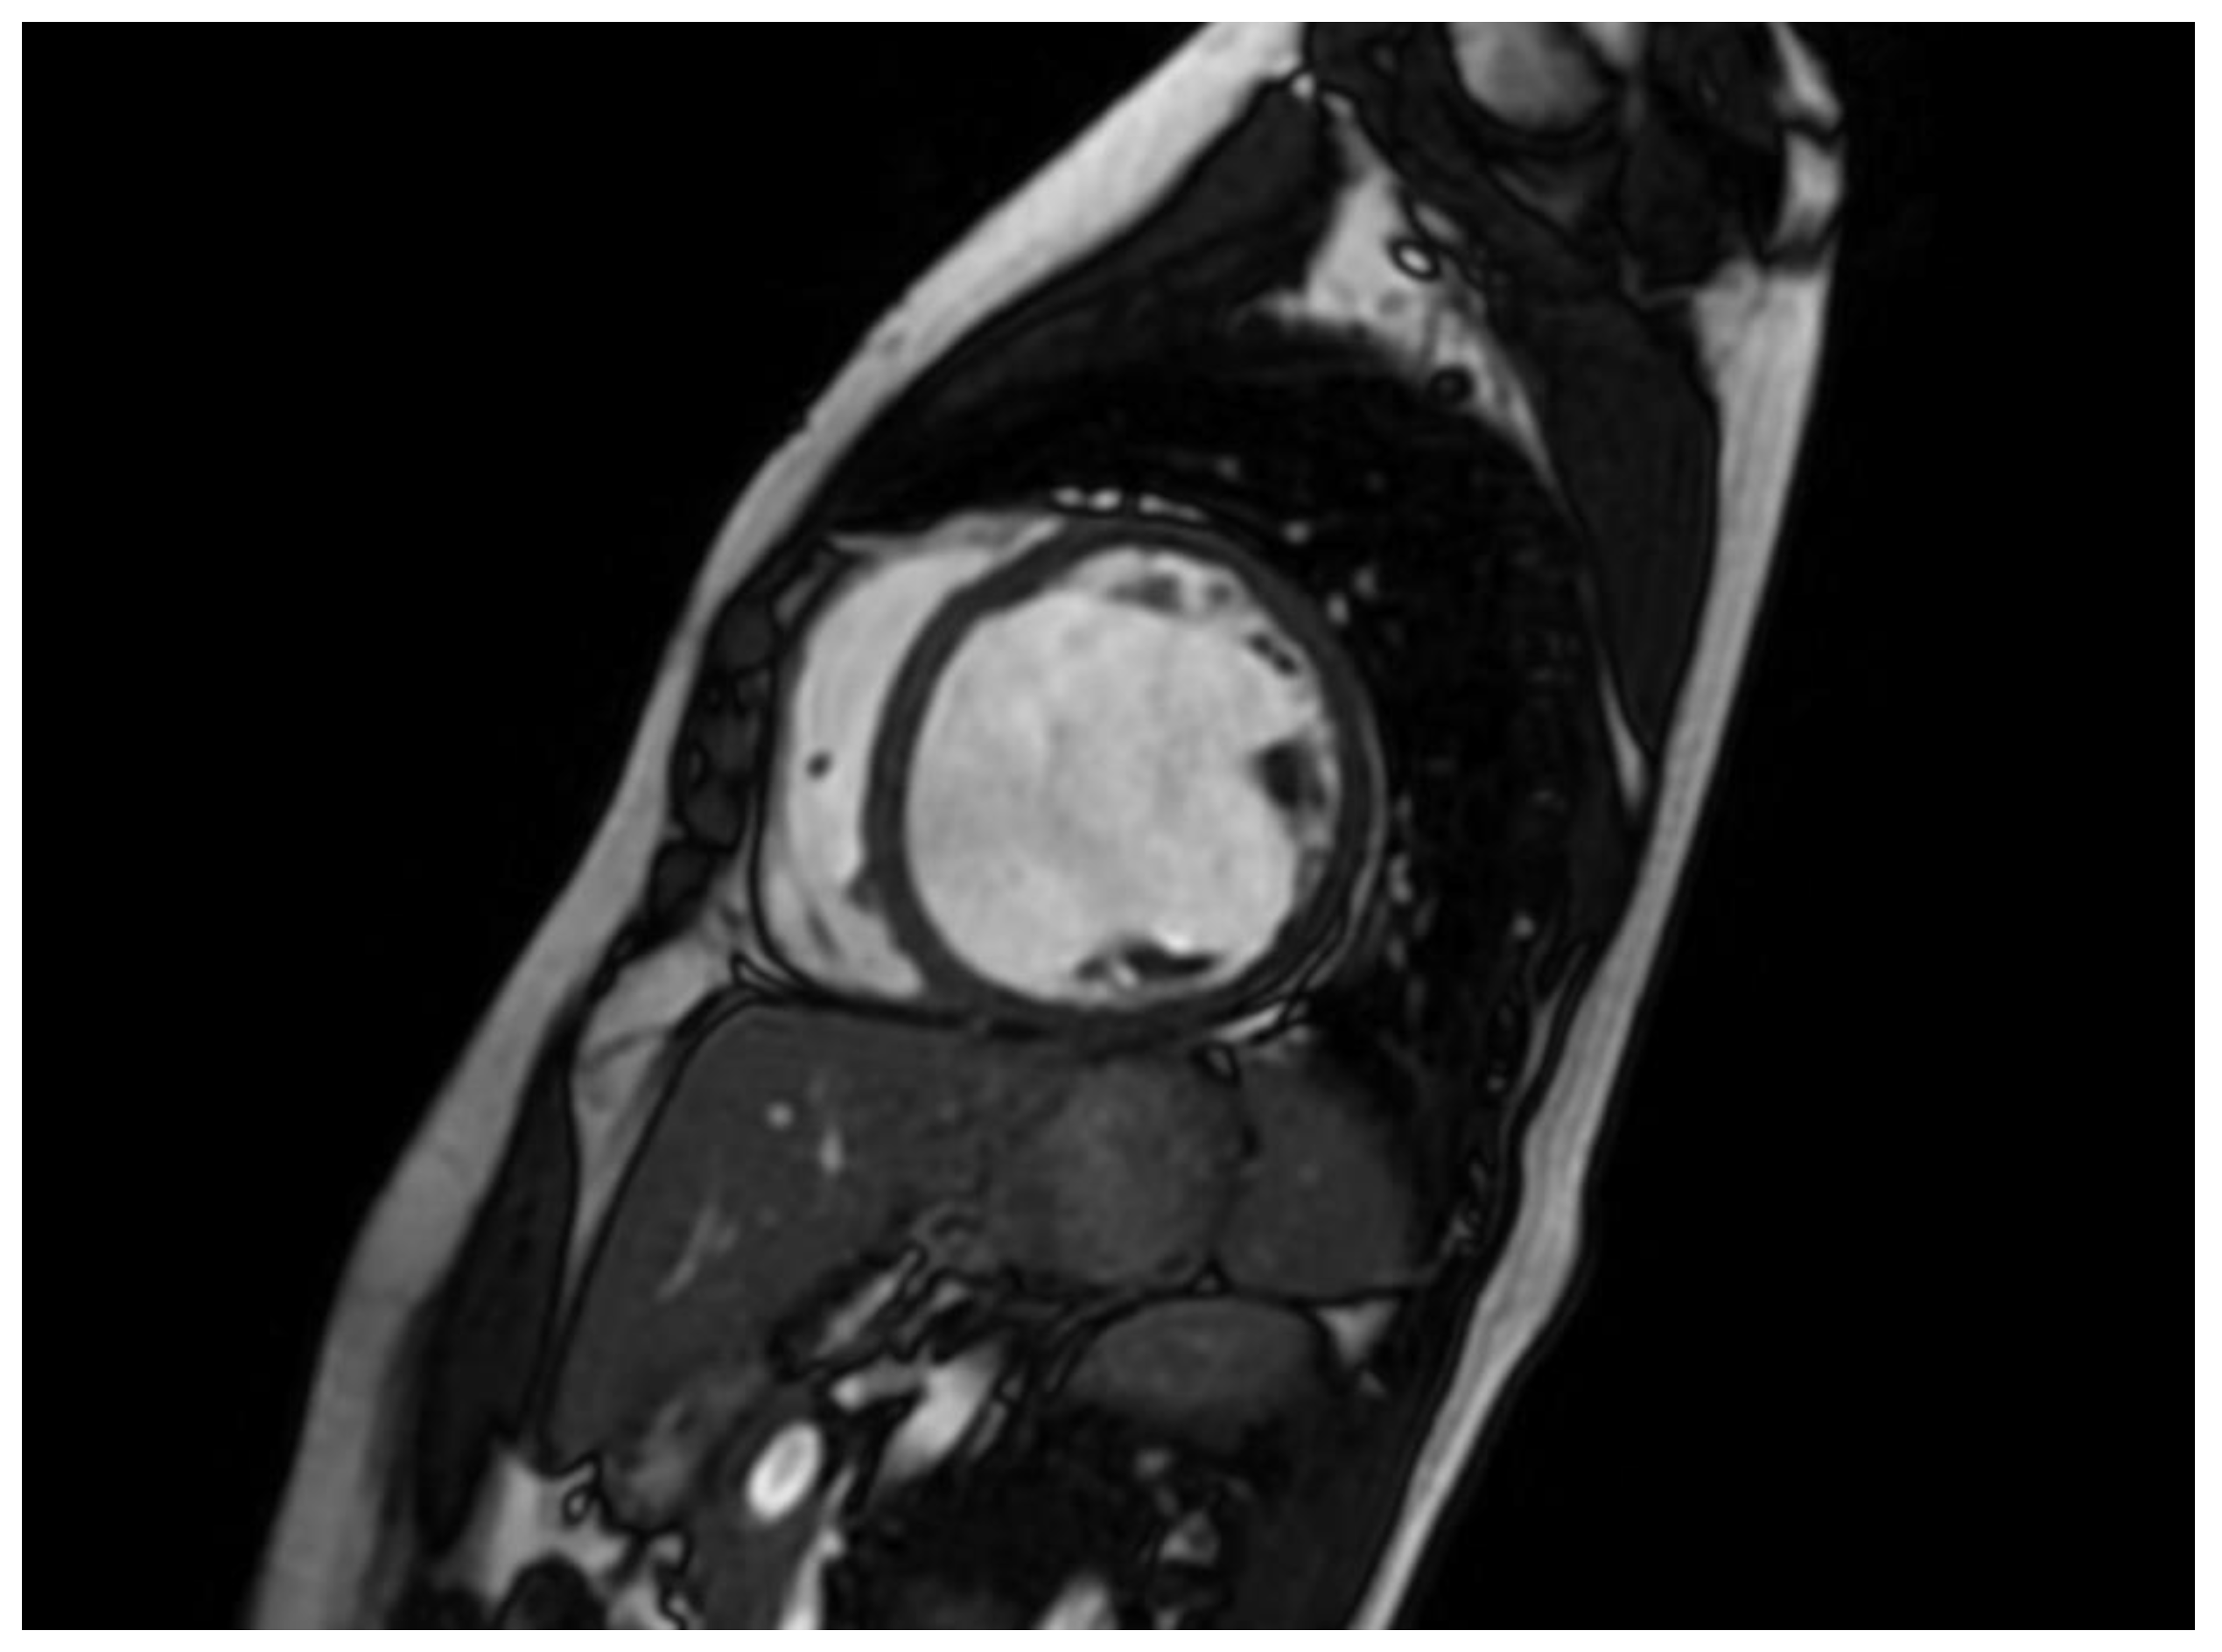

CMR imaging has become the most reliable method for evaluating the size and function of the ventricles. It should be performed in all patients who have recently been diagnosed with cardiomyopathy. CMR can offer comprehensive anatomical and physiological data that surpasses that of TTE. Additionally, CMR can provide insights into cardiac tissue features, including inflammation and fibrosis, through the use of late gadolinium enhancement (LGE). CMR has the benefits of being non-invasive and not requiring an acoustic window, while also allowing for the analysis of tissue characteristics. The latter benefit is especially crucial in diagnosing non-compaction LV cardiomyopathy (Figure 4) , ARVC, myocarditis, amyloidosis, sarcoidosis, and other types of inflammatory diseases, as well as haemochromatosis. Standard initial examination should regularly include cine imaging sequences, T2-weighted sequences, pre- and post-contrast T1 mapping, and LGE. These findings should be evaluated alongside genetic results and other clinical features by experienced professionals in cardiac imaging and heart muscle disease assessment.

Regular follow-up CMR should be conducted every 2-5 years, depending on the initial severity and clinical course of the disease. This can help assess the progression of the disease and the effectiveness of therapy [4]. The existence of LGE is linked to the possibility for arrhythmias and more severe illness. Diseases connected to DSP and FLNC frequently exhibit a fibrosis pattern resembling a ring around the outer layer of the heart, known as subepicardial fibrosis. This observation may suggest the need for considering the installation of an implantable cardioverter-defibrillator (ICD). CMR has the capability to identify illness in persons who do not show any symptoms and may also be used to track the progression of the disease [68].

The existence of LGE is linked to the possibility for arrhythmias and more severe illness. Diseases connected to DSP and FLNC frequently exhibit a fibrosis pattern resembling a ring around the outer layer of the heart, known as subepicardial fibrosis, as presented in Figure 5. This observation may suggest the need for considering the installation of an implantable cardioverter-defibrillator (ICD). CMR has the capability to identify illness in persons who do not show any symptoms and may also be used to track the progression of the disease [68].